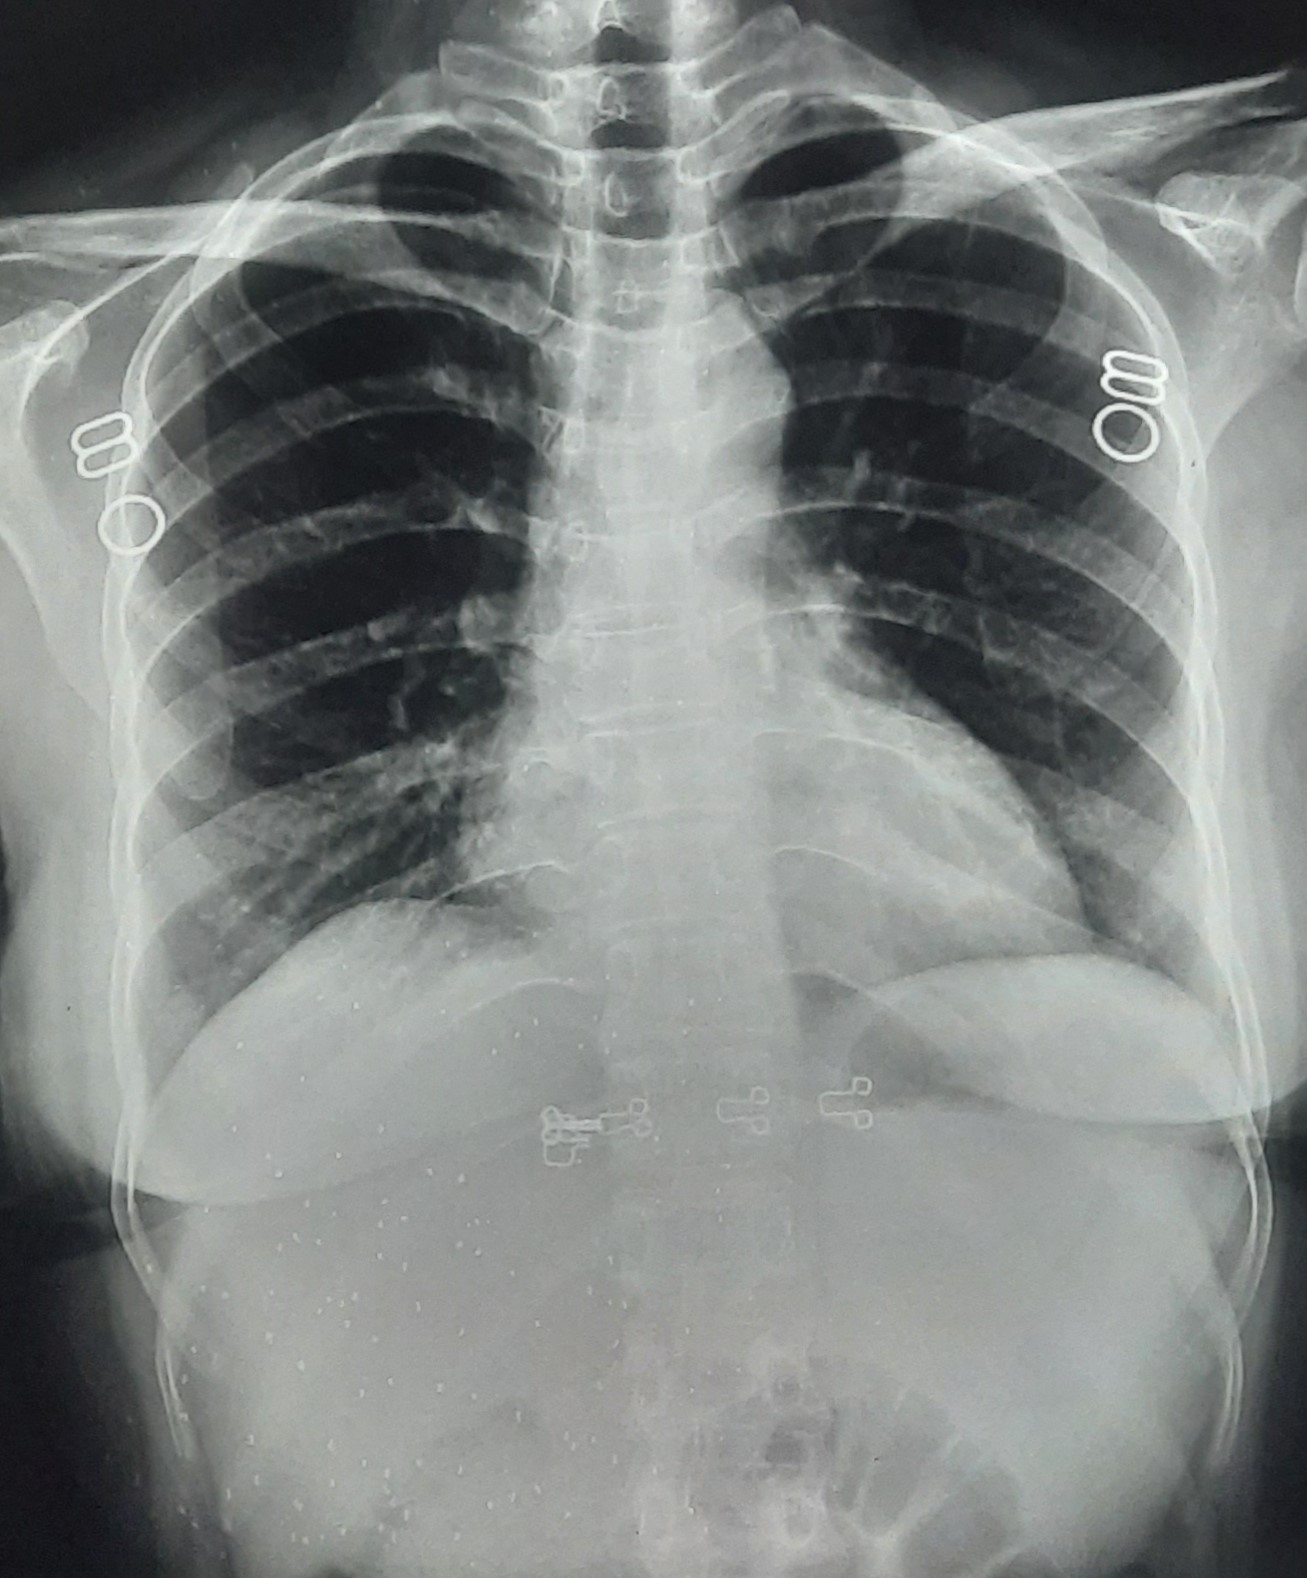

| 338 | IGGMC, Nagpur, Nagpur | P2 | 29-4134 | Rupesh Dongse | Consent taken on Paper | 43 Yrs. |

Provisional Diag : Consolidation

Final Diag : Bilateral Consolidation Community Acquired Pneumonia With Type 1 Respi Failure In Cronic Alcoholic |

Non-TB Case (Confirmed) | Bilateral Consolidation | Abnormality visible on x-ray |